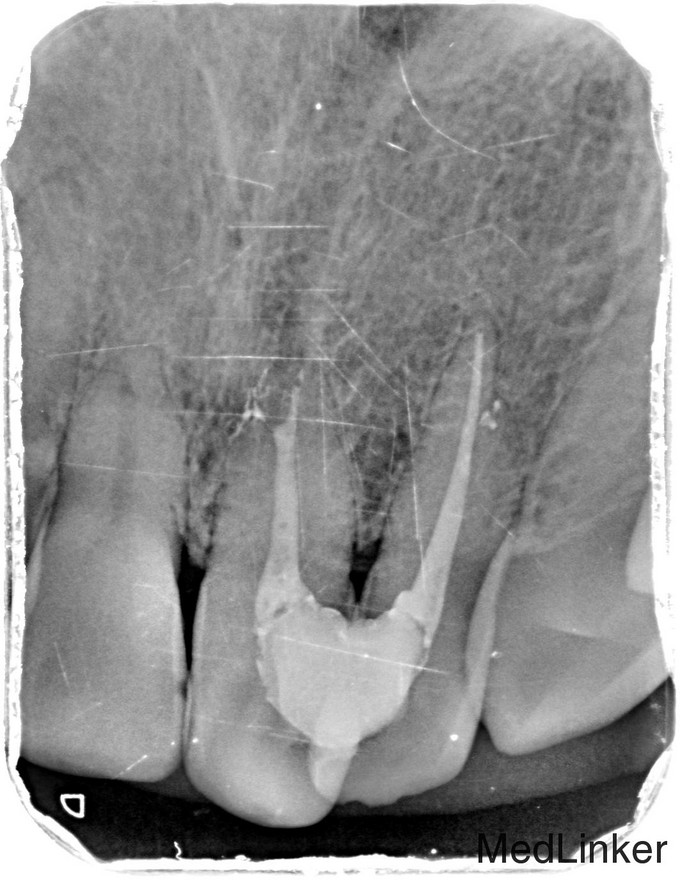

临床检查:21,22之间邻面龋坏,探(++),冷(++),叩(-),松动度(-),可探及穿髓点,无窦道,牙周红肿。 辅助检查:X线示21,22龋坏累积髓腔,根尖周牙周膜增宽。

诊断:21,22牙髓炎 治疗:经患者知情同意后,21,22局麻去腐,开髓拔髓寻找根管口,建立直线通路,扩通根管,确定工作长度。S3/EDTA凝胶镍钛器械,低浓度次氯酸钠冲洗根管,预备至30/06,试主尖X线示恰充,试干根管,导AH-PLUS糊剂,VDW热压胶垂直加压根充,术后见根管恰充,垫底树脂充填。调合术后24小时抛光。